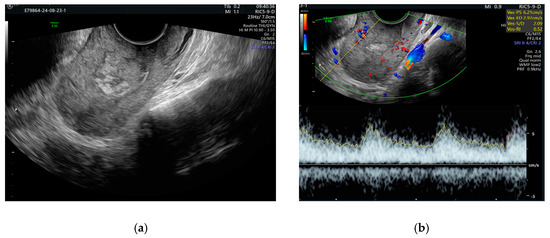

2. Case Presentation